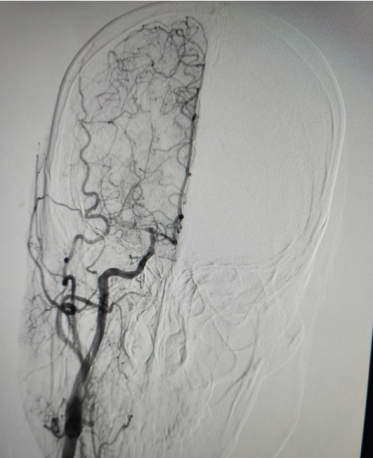

术中所见:

左侧大脑中动脉近端闭塞,新生血管形成呈烟雾状,由左侧大脑前动脉及大脑后动脉经脑膜支代偿。

右侧大脑后动脉重度狭窄。